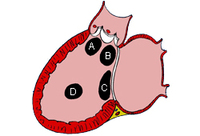

Subtipos de comunicaciones interauriculares: (A) seno venoso; (B) ostium secundum; (C) ostium primum; (D) seno coronario sin techo